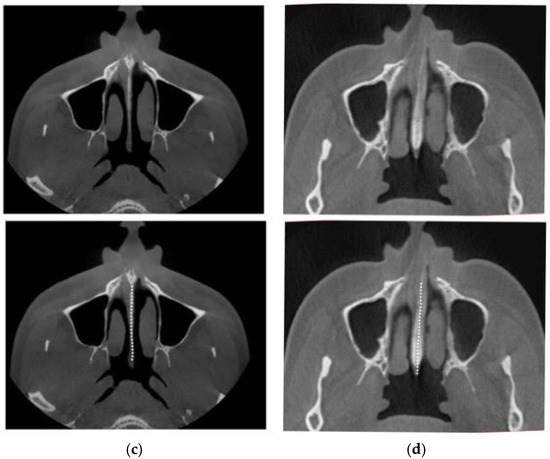

2.5. Case B: Guide-Assisted Midpalatal Piezocorticotomy

2.6. Case C: Bilateral Posterior Crossbite with Guide-Assisted Expansion